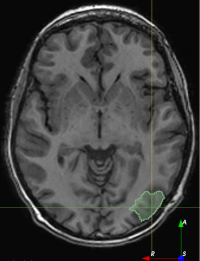

Figure 5: Resection simulations 𝑿Rsubscript𝑿𝑅\bm{X}_{R} generated using our method.

Refer to caption

(a)

(b)

(c)

(d)

(e)